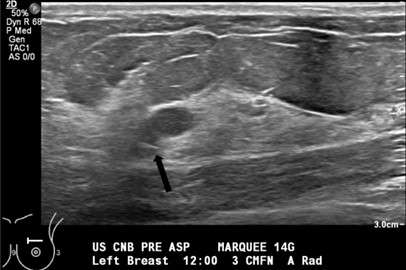

Technologist confirms the lesion is still visualized and saves a pre-procedure image (Figure 1).

Figure 1. Grayscale sonogram shows two adjacent well-circumscribed, anechoic cysts at 12:00, 3 cm from the nipple.- Radiologist performs time out and confirms patient identity, procedure, and side.